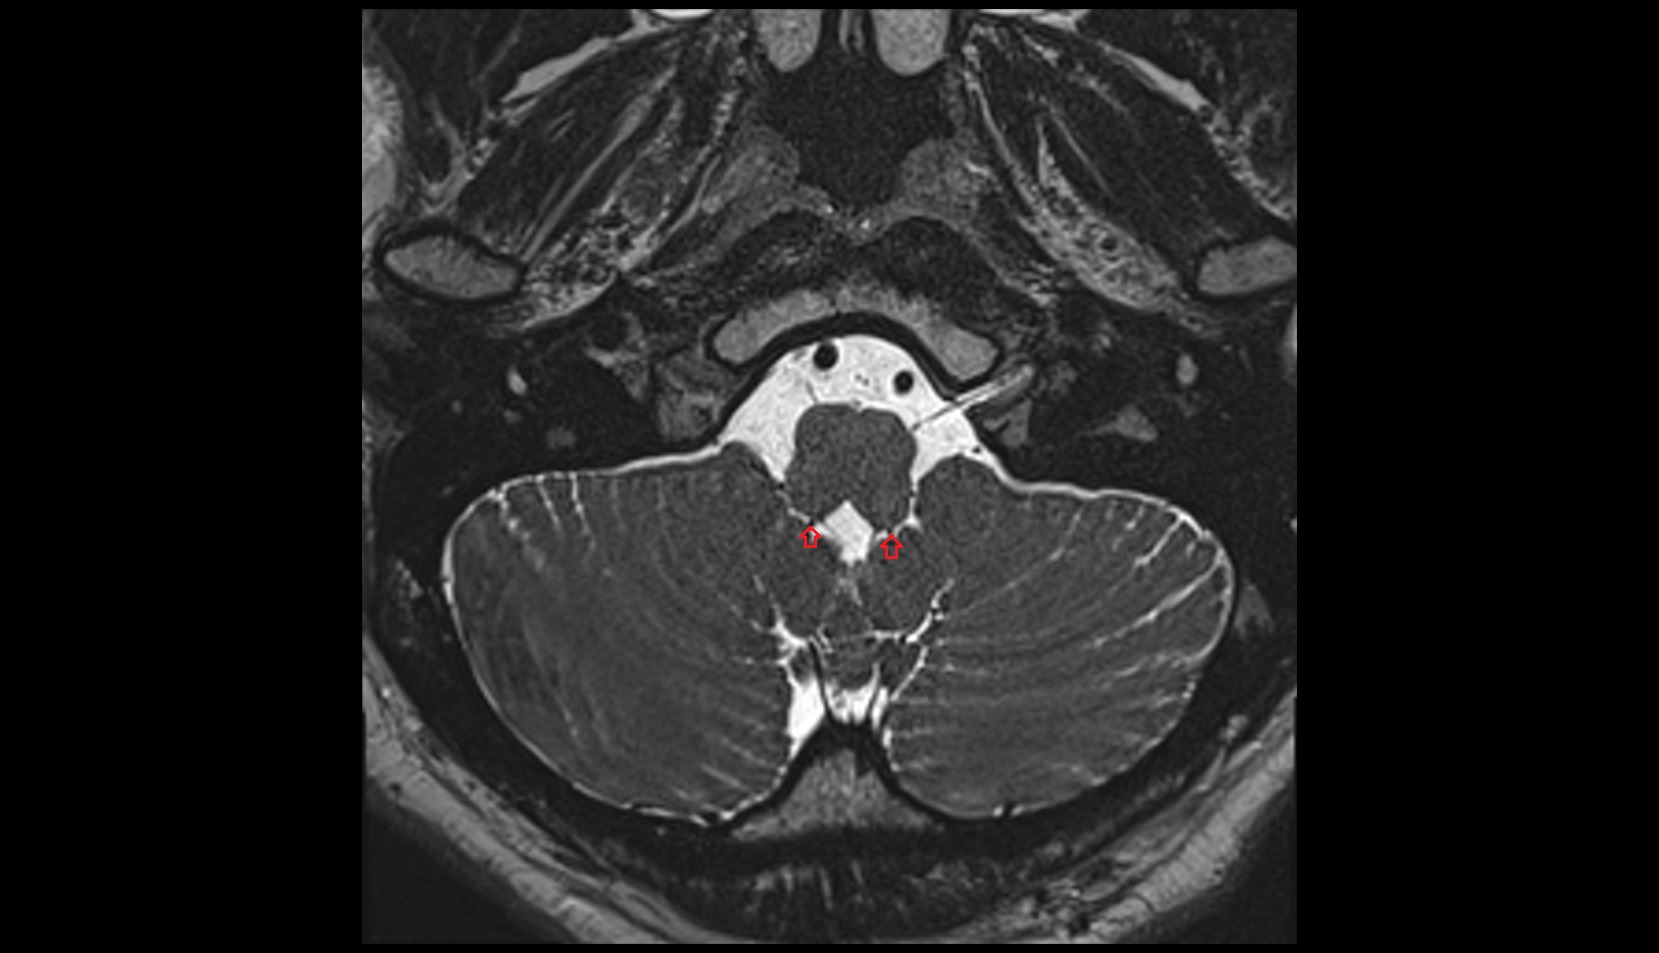

- Peripheral zone of prostate

- Anterior Fibromuscular Stroma of prostate

- Central zone of prostate

- Transitional zone of prostate